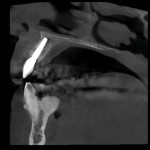

A 78-year-old female patient presented to the practice for an emergency visit because her left lateral incisor (tooth No. 10) had fractured at the gumline. She reported that she was "simply biting into a sandwich when her tooth broke off." The patient had a long history of consistent dental care throughout her life, and more than 30 years ago, tooth No. 10 had been previously restored with a root canal treatment, post and core buildup, and a porcelain-fused-to-metal (PFM) crown. Upon examination, it was noted that tooth No. 10 was fractured with no coronal tooth structure left and that a vertical root fracture was present. The tooth was deemed non-restorable. Treatment options were presented to the patient, and the risks and benefits of an implant-supported restoration versus a fixed partial bridge were discussed. If possible, the patient decided that she would like an implant placed. Her fractured PFM with its intact post and core was temporarily re-cemented that day and the patient was appointed to return for records.